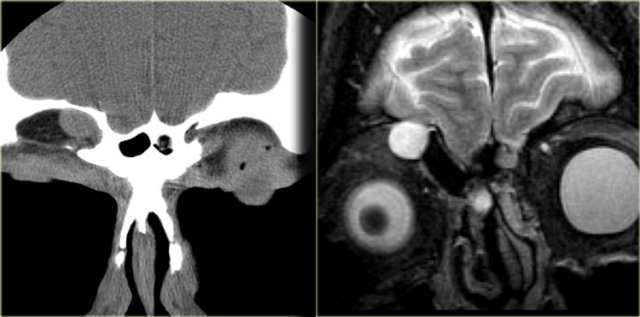

On the left a T2W-image in an immuno-compromised patient with fever.

Initially a MRI was performed to rule out sinusitis.

Notice the low signal intensity of the left sphenoid sinus, which also had a low signal intensity on the T1W-image (not shown).

Continue with the CT.

Pseudo-pneumatized sinus on MR. Beware of fungus! Pseudo-pneumatized sinus on MR. Beware of fungus!

The CT clearly shows the opacified sinus, which is slightly hyperdense.

The signal characteristics on MRI and the attentuation on CT are a result of the high protein content of fungus.

This is a good example of the pitfall of the 'pseudo-pneumatized sinus' .

This is an example of an Actinomyes infection.

So, when invasive fungal infection is suspected, start with a CT, then move on to MRI to rule out spread to the eye, cavernous sinus and intracranial compartment!